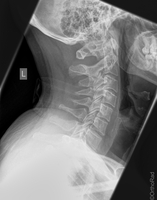

Wirbelsäule